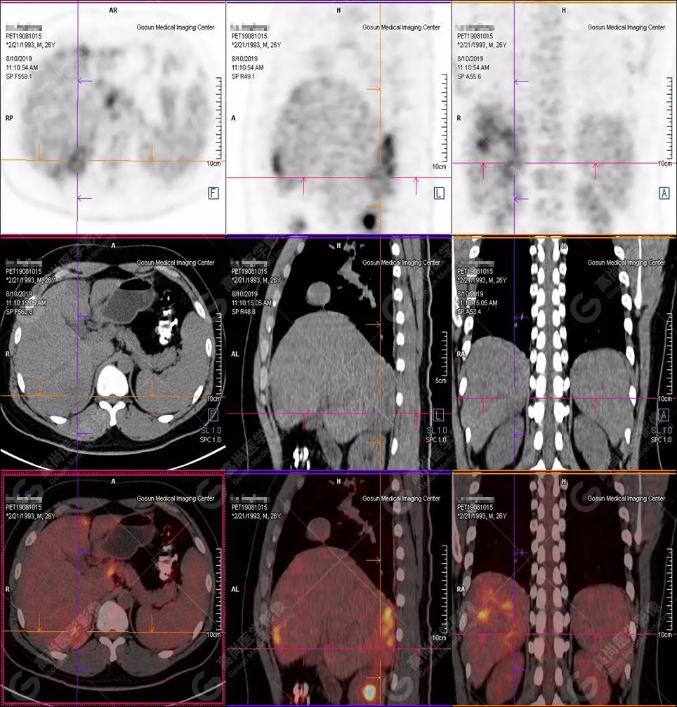

PET/CT全身圖

PET/CT診斷

嗜酸性粒細(xì)胞增多癥肝浸潤